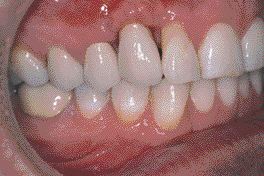

FIGURE 12--Completed case.